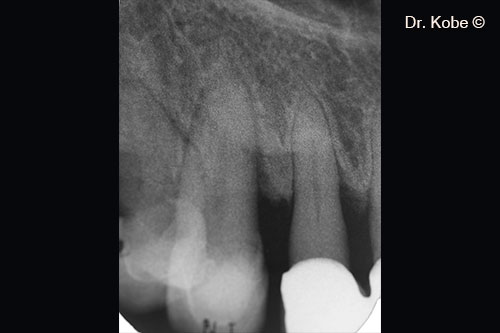

Vertical bone defect on the radiograph